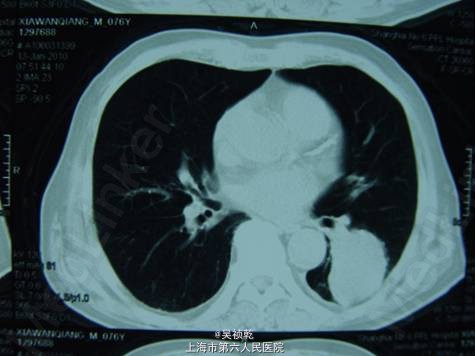

查体:浅表淋巴结(-)既往无重大疾病,体重下降5kg,肿瘤CEA>1500 ug/L。胸部CT :左下肺占位,考虑转移。上腹部CT :肝脏多发转移。盆腔CT :直肠肿物,伴不全肠梗阻。

术前诊断:直肠癌伴肝肺转移(肝脏多发,肺单发) 行直肠癌TME手术:术中探查:肝脏多发转移结节,最大者4cm, 无腹水及腹盆腔种植结节; 直肠肿瘤距肛门8cm,侵犯浆膜外脂肪组织。 病理:溃疡型管状腺癌II级,4.5*3.5*2cm,侵至肠壁全层,达肠周脂肪组织,肠周淋巴结转移: 6/12,肠系膜动脉根部0/2淋巴管(+)神经周围(+)血管(+)。K-ras检测:野生型 术后行化疗方案为:FOLFOX 4+Cetuximab (q2wk * 6次) 后评估肿瘤部分缓解,6次化疗结束后改为XELOX / q3wk*6次,评估肿瘤无进展。 下图可见复查的影响学资料相比化疗前肿瘤有明显缩小。